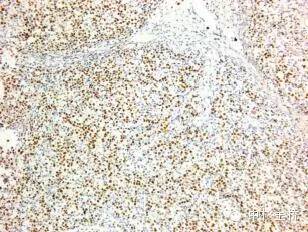

圖為EBER原位雜交染色DBA顯色,蘇木素復(fù)染

EBER是EB病毒編碼的小RNA,在EB病毒感染的細(xì)胞核中高拷貝存在。根據(jù)EBER的序列設(shè)計(jì)的EBER RNA探針,可以用于石蠟切片,具有較高的特異性和靈敏度,該試劑盒廣泛應(yīng)用于美國(guó)、歐盟等各國(guó)。

- DAB顯色,永久保存